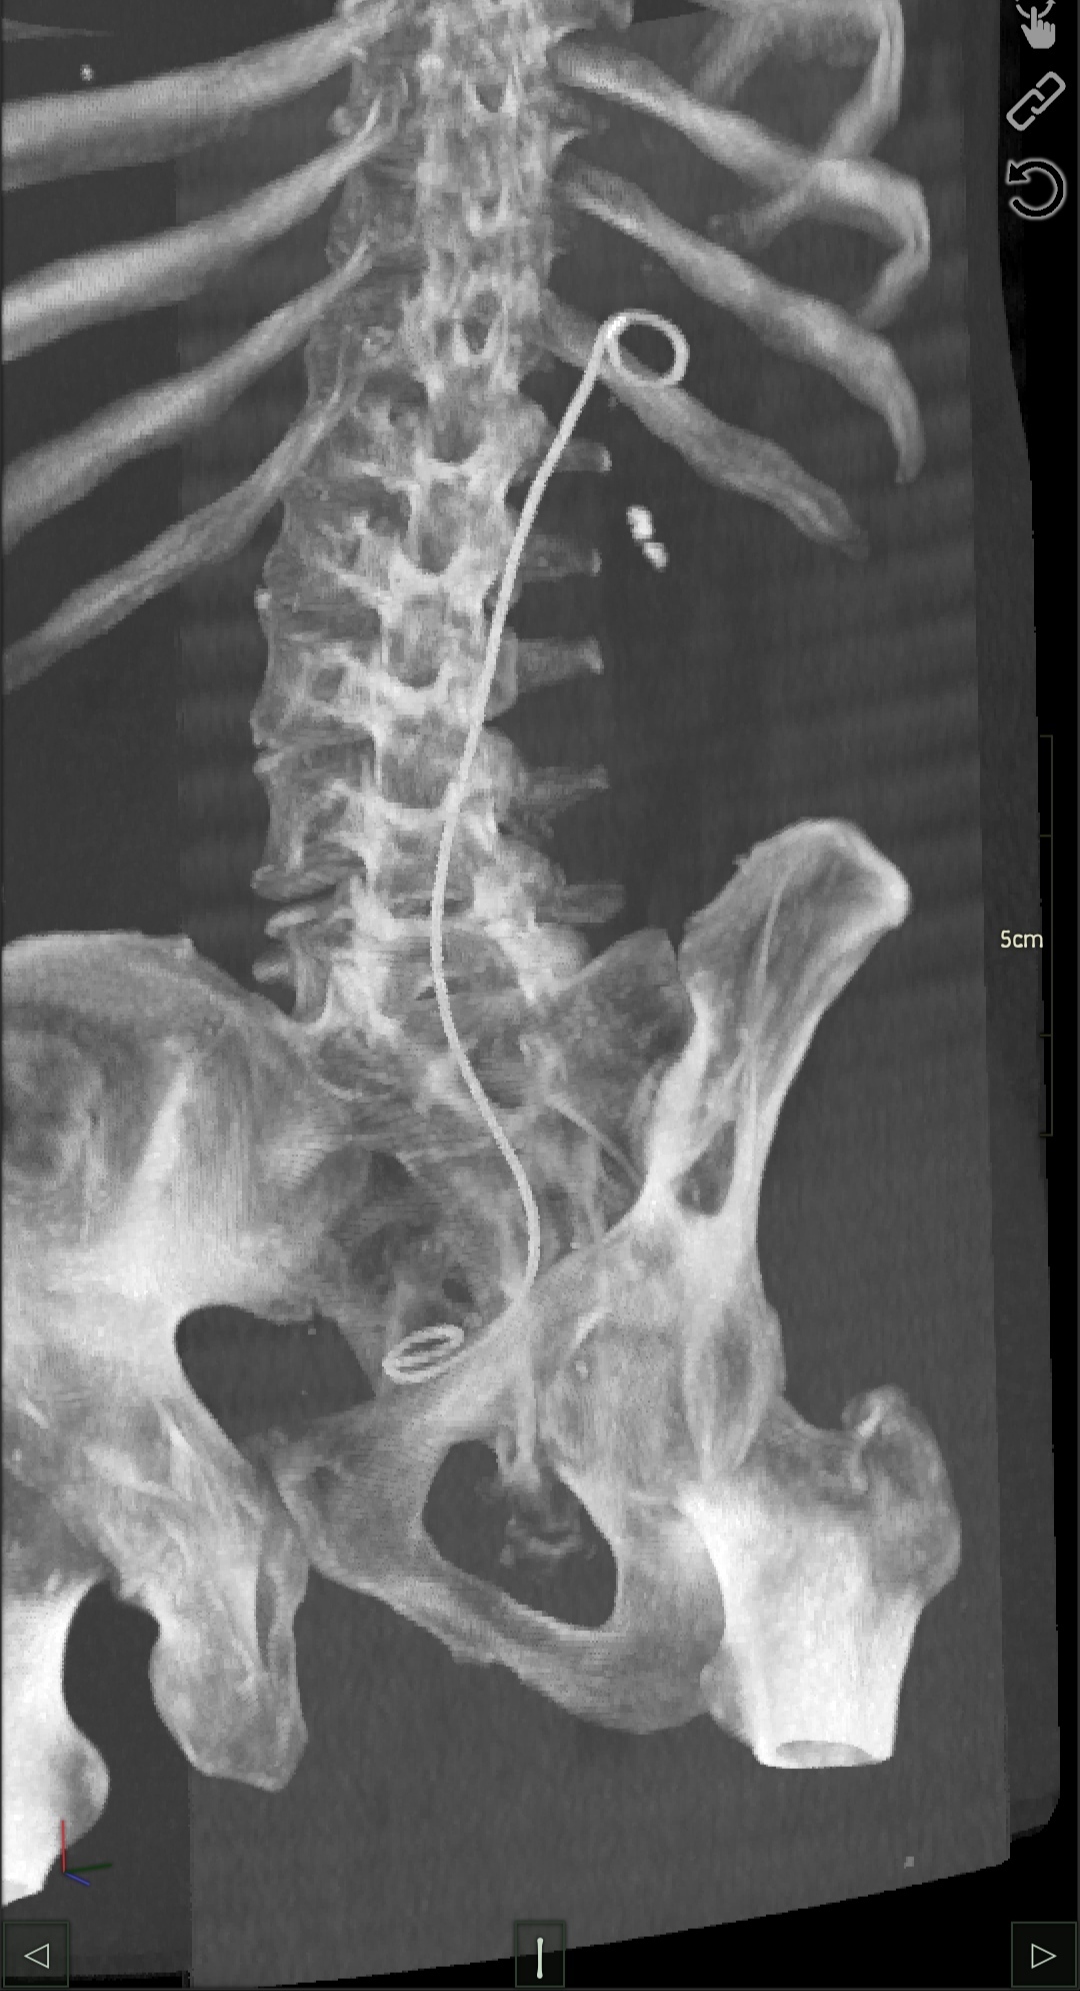

Автор поста оценил этот комментарий

Иллюстрация к комментарию

5